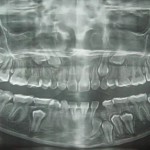

Carcinoma squamocellulare: conoscerlo per prevenire e curare

La diagnosi precoce del carcinoma squamocellulare orale ha un'importanza fondamentale nella sopravvivenza e incide incredibilmente sulla qualità di vita dei pazienti che ne sono...